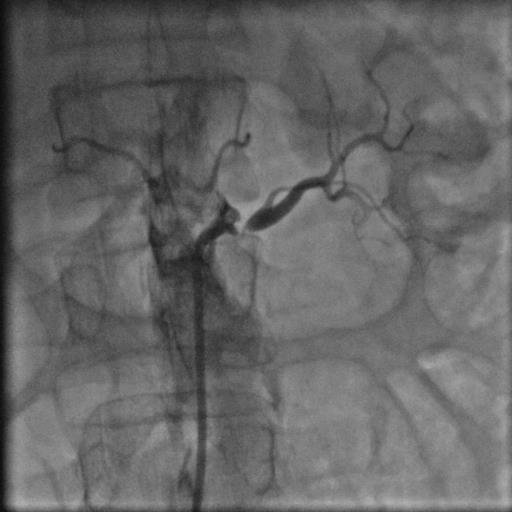

44 yaşında şeker hastalığı olan hastamız dirençli yüksek tansiyon şikayetiyle bize başvurdu. Herhangi bir sebep bulunamayan hastamız 2 yıldan beri cesitli ilaçlar kullanmasına rağmen tansiyonunun düşürülemediğini söylüyordu. Yaptiğımız detaylı muayene ve tetkikler sonucu böbrek damarının tıkalı olduğunu tesbit ettik ve yaptıgımız stent işlemi sonrasında hastamız normal tansiyon değerleriyle taburcu edildi..